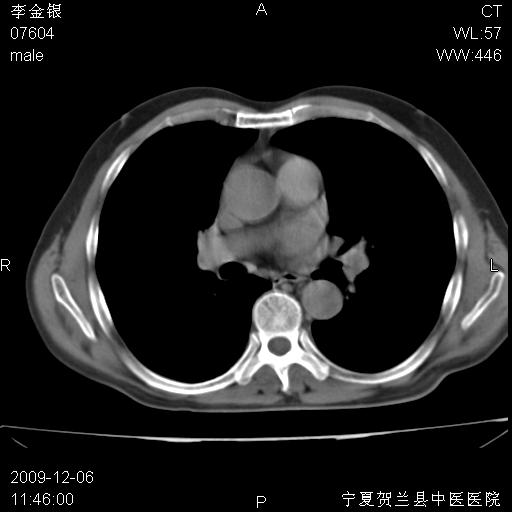

该病人 ,男,62岁,主因咳痰带血两天

考虑右肺中央型占位性病变并阻塞性肺炎.(右肺上叶支气管变窄),建议支纤镜检查.

考虑右肺中心型肺癌伴阻塞性肺炎及右肺门淋巴结转移,建议纤维支气管镜进一步检查。

支气管壁明显增厚 管腔狭窄,腔静脉后多个淋巴肿大,结合年龄病史考虑右肺上叶中央型肺癌并阻塞性肺炎

右肺上叶后段支气管阻塞,右上肺门占位,相应肺段阻塞性肺炎,右肺门有淋巴结肿大。诊断右肺上叶中心型肺癌,阻塞性肺肺炎、右肺门淋巴结转移。

右上叶支气管狭窄,管壁增厚,远端斑片状软组织影,病灶邻近叶间裂,叶间裂无移位。

诊断右肺中央型肺癌。

那个片影应该大部分都是病灶,病灶沿肺段支气管分支生长,后段完全显示不清、闭塞。若为不张应该伴有叶裂的移位,若为炎症应有空气支气管征。

右肺中心型肺癌伴阻塞性肺炎及右肺门与纵膈淋巴结转移很典型,可纤维支气管镜进一步检查

考虑右侧中央型肺癌伴右肺上叶后段阻塞性炎症、肺不张、右肺门和纵隔淋巴结肿大。

右肺上叶中心型肺癌,阻塞性肺炎、右肺门和纵隔淋巴结转移。